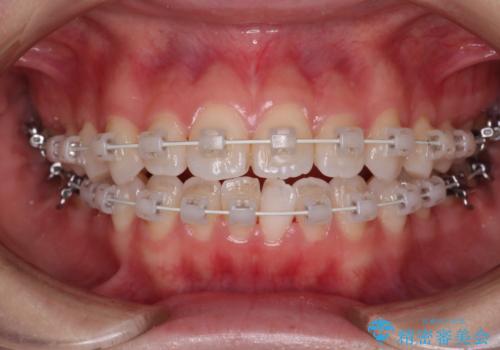

【審美装置】前歯で噛めない!抜歯しないで治したい

- 前歯の捻転とかみ合わせを主訴に来院されました。今回は抜歯をせずにIPRを実施し、並べる計画を立てました。

ワイヤー矯正を行いながら、顎間ゴムを患者さまにご協力していただき、短い期間で終了できました。